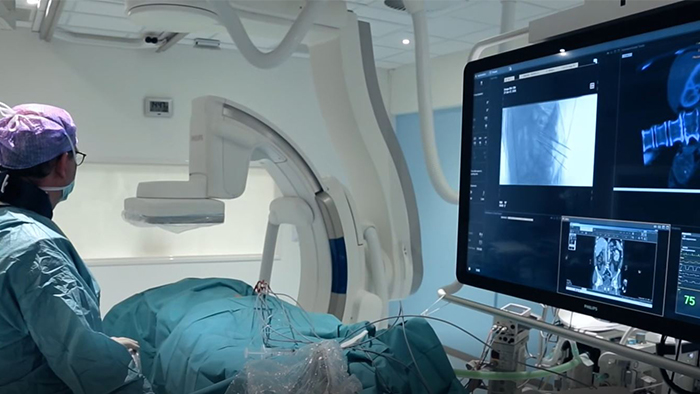

Azurion’ s next leap in lab integration and 3D imaging gives you control over an array of compatible applications from a single touch screen interface at table side. Extend the life of your interventional lab with a SmartPath catalyst conversion or enable advanced and complex procedures in the fields of interventional radiology, cardiology, neuroradiology, oncology and surgery.

Our imaging technology ClarityIQ, combines advanced, real-time image noise reduction algorithms with state-of-the-art hardware. Together, they form a flexible digital imaging pipeline designed to perform individual image processing algorithms more efficiently. This unlocks superb visualization and significant dose reduction capabilities for healthcare facilities. ClarityIQ is available as an option on Azurion systems.

Every day you navigate some of life’s most challenging situations amidst the complexities of modern healthcare. Your work inspires us to develop more seamless solutions – to help you decide, guide, treat, and then confirm the right care, for every patient, in real time.

Today, the Philips portfolio of image-guided therapy (IGT) solutions uniquely integrates best in class imaging systems and software, with specialized diagnostic and therapeutic devices to support exceptional treatment for even the most complex procedures.